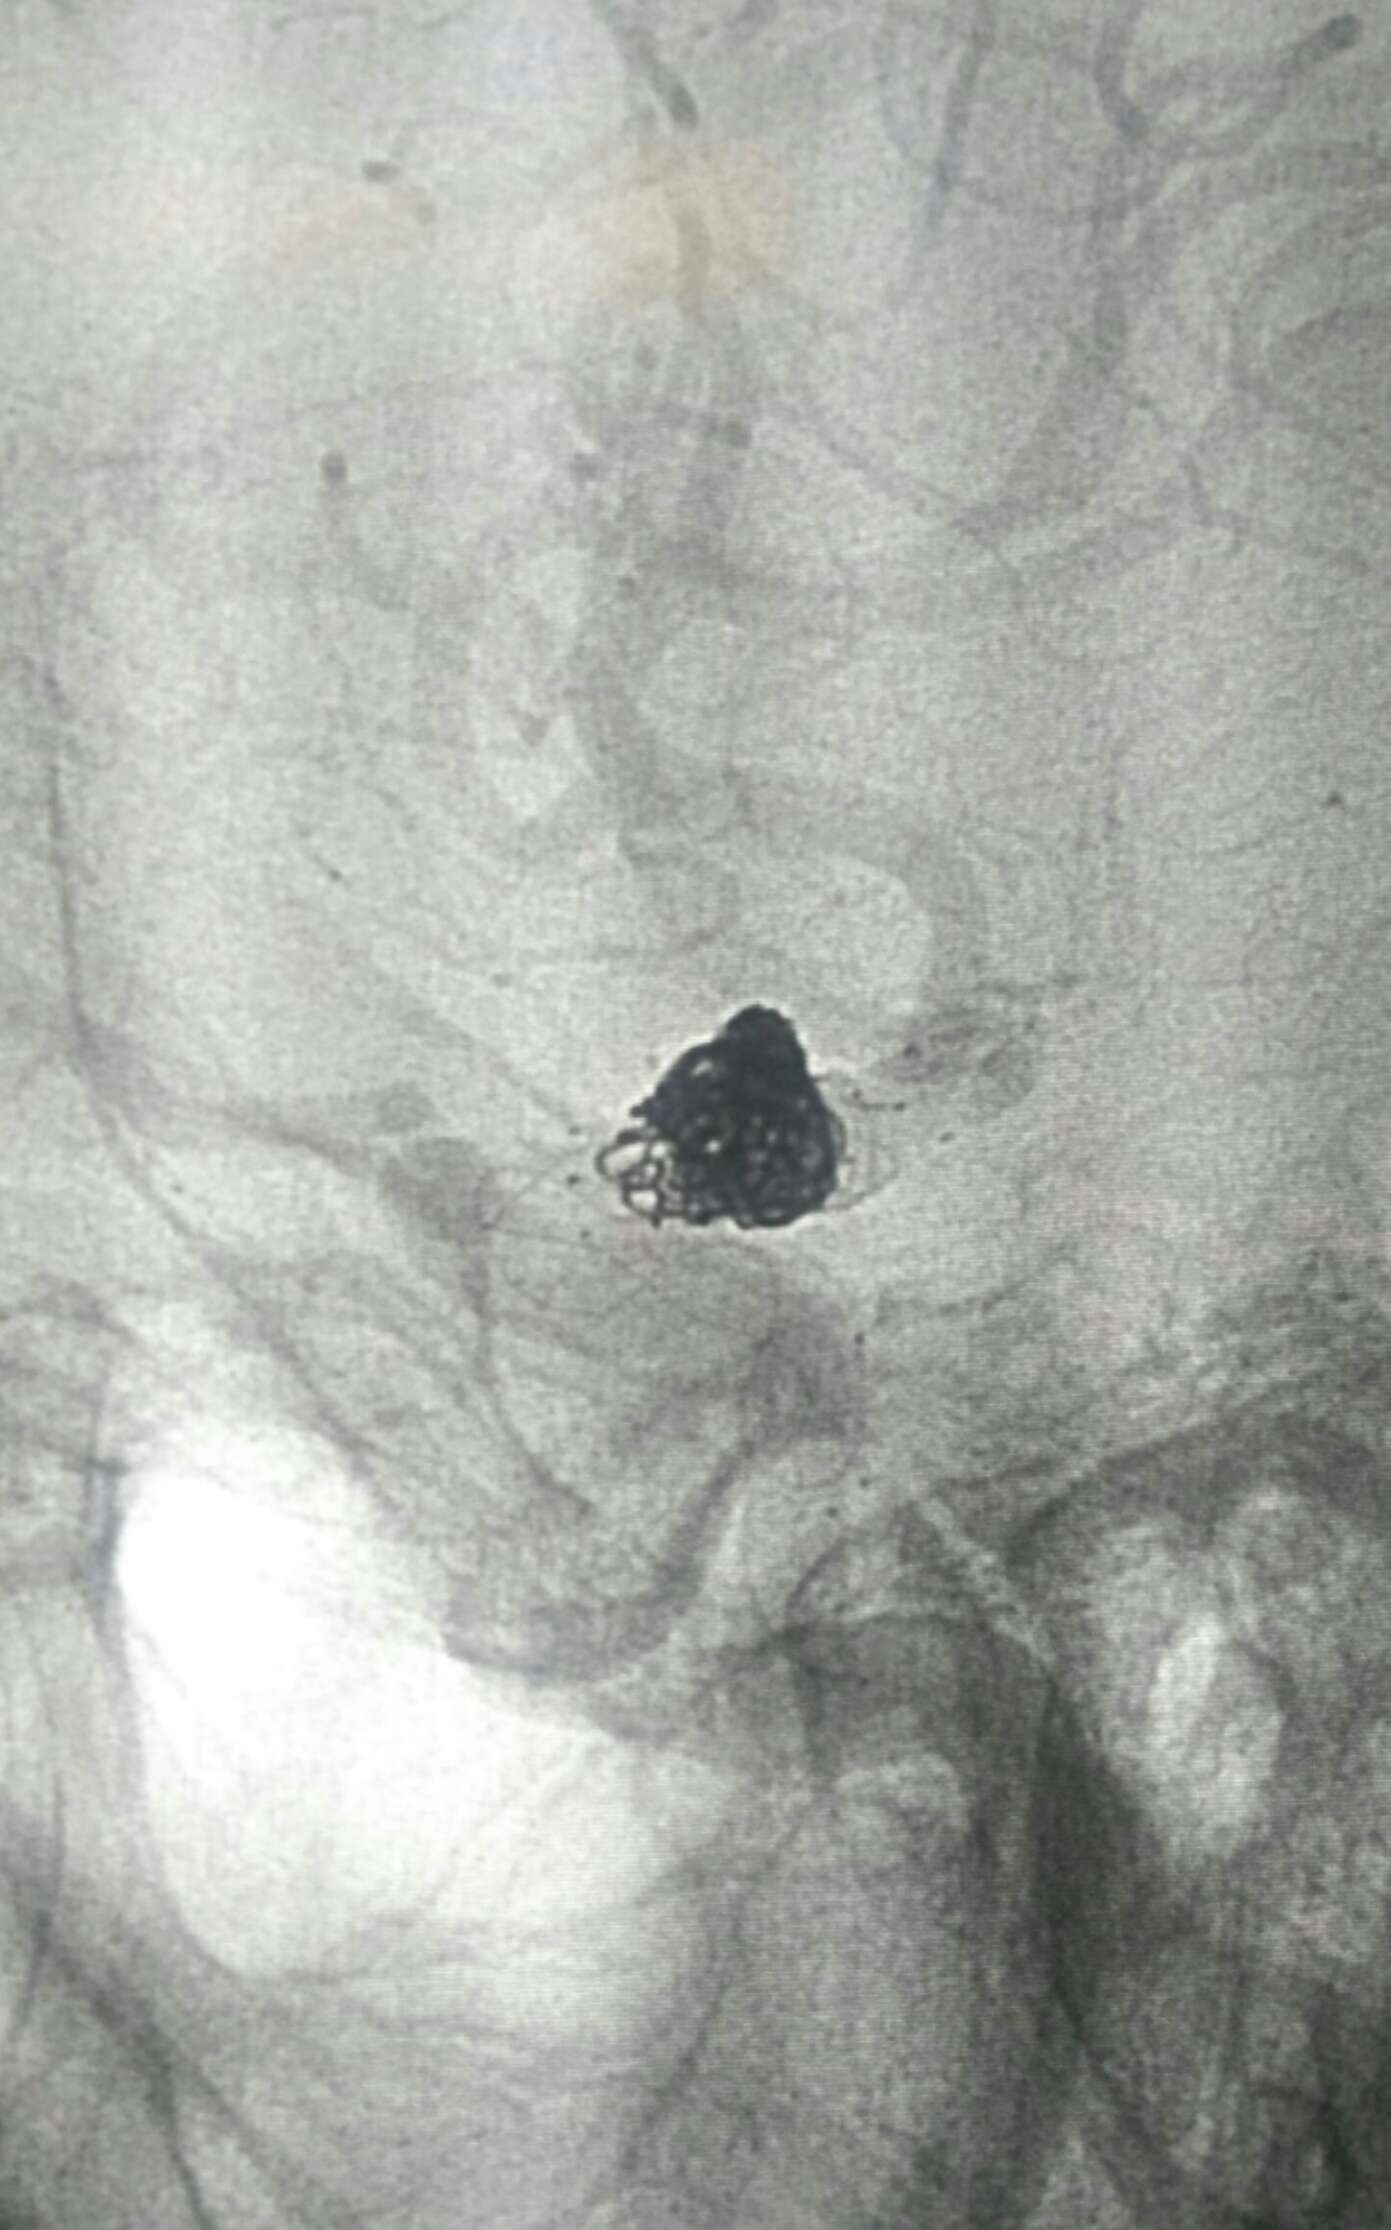

术后20天复查造影动脉瘤栓塞良好无复发显影。目前四肢活动正常,不完全运动性失语,继续康复!

侧位

显示支架

复查3D